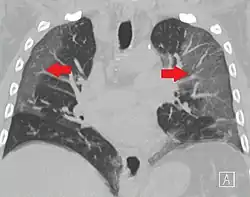

High-resolution CT image showing ground-glass opacities in the periphery of both lungs in a patient with COVID-19 (red arrows). The adjacent normal lung tissue with lower attenuation appears as darker areas.

Ground-glass opacity is among the most common imaging findings in patients with confirmed COVID-19.[16][17] One systematic review found that among patients with COVID-19 and abnormal lung findings on CT, greater than 80% had GGOs, with greater than 50% having mixed GGOs and consolidation.[16] GGOs with mixed consolidation has most often been found in elderly populations.[18]

Several studies have described a pattern among initial, intermediate, and hospital discharge imaging findings in the disease course of COVID-19. Most commonly, initial CT imaging reveals bilateral GGOs at the periphery of the lungs. During initial stages, this is most often found in the lower lobes, although involvement of the upper lobes and right middle lobe has also been reported early in the disease course.[16][18] This is in contrast to the two similar coronaviruses, SARS and MERS, which more commonly involve only one lung on initial imaging.[19][20] As the COVID-19 infection progresses, GGOs typically become more diffuse and often progress to consolidation.[11][18] This is sometimes accompanied by the development of a crazy paving pattern and interlobular septal thickening.[18] In many cases the most severe pulmonary CT abnormalities occurred within 2 weeks after symptoms began.[17] At this point, many individuals begin showing resolution of consolidation and GGOs as symptoms improve. However, some patients have worsening symptoms and imaging findings, with further increase in septal thickening, GGOs, and consolidation. These patients may develop lung "white-out" with progression to acute respiratory distress syndrome (ARDS) requiring treatment escalation.[17][21]